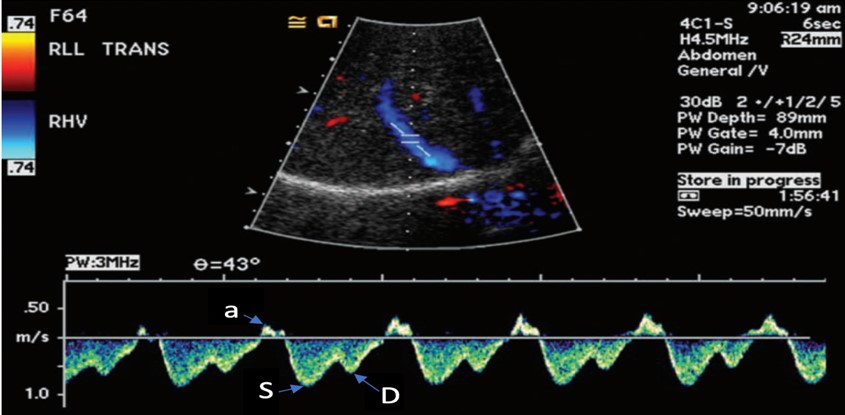

Once a view is obtained, a pulsed wave doppler should be placed within the hepatic vein, attempting to position at an angle parallel to the flow of the vessel for optimal waveform (Figure 2).

Figure 2. Normal hepatic vein Doppler (S>D wave)7

a= atrial kick

S= atrial systolic filling

D= atrial diastolic filling

The venous flow within the hepatic veins can be best thought of as a central venous pressure (CVP) tracing from the right atrium, reflecting the cardiac cycle of the right heart. Understanding this, the hepatic venous doppler waveform helps not only in the evaluation of venous congestion but also right heart function. The typical CVP tracing reveals an atrial kick, followed by systolic and diastolic filling of the atrium. A normal hepatic venous doppler will reveal a retrograde “a” wave followed by two antegrade “S” and “D” waves, as seen in Figure 2. A normal waveform consists of a relatively small a wave with the S wave larger than the following D wave (S>D), as a there is greater primary venous flow into the atrium during systole. As the venous system becomes engorged, the S wave becomes smaller relative to the D wave (S<D), due to a physiologic change from primarily systolic filling to a relative increase in passive diastolic filling of the heart (Figure 6A). As congestion continues, there is S wave reversal as seen in Figure 6B. The relative doppler flows noted in these tracings can thus help determine whether the heart is providing sufficient forward flow to prevent further venous engorgement, as well as help in the identification of right heart lesions, such as tricuspid regurgitant flows. Regurgitant flows may affect the pressures that are placed on the venous system. As such, hepatic vein flows can provide critical information about how the heart functions in response to increased venous congestion and determine when we have strained the heart to a point where it may benefit from de-resuscitation.